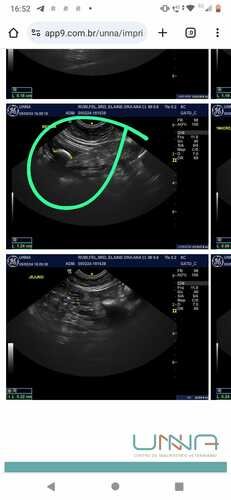

Infelizmente, a Rubi foi diagnosticada com cistolitíase (pedra na bexiga de grande proporção) e precisa realizar com urgência a retirada do cisto, isso custará R$ 800, 00 mais medicações e no momento não temos condições de pagar. Como membros da nossa comunidade felina, sabemos que vocês entendem o vínculo especial que compartilhamos com nossos animais de estimação. Qualquer contribuição, por menor que seja, fará uma enorme diferença para garantir que ela receba o tratamento de que precisa.